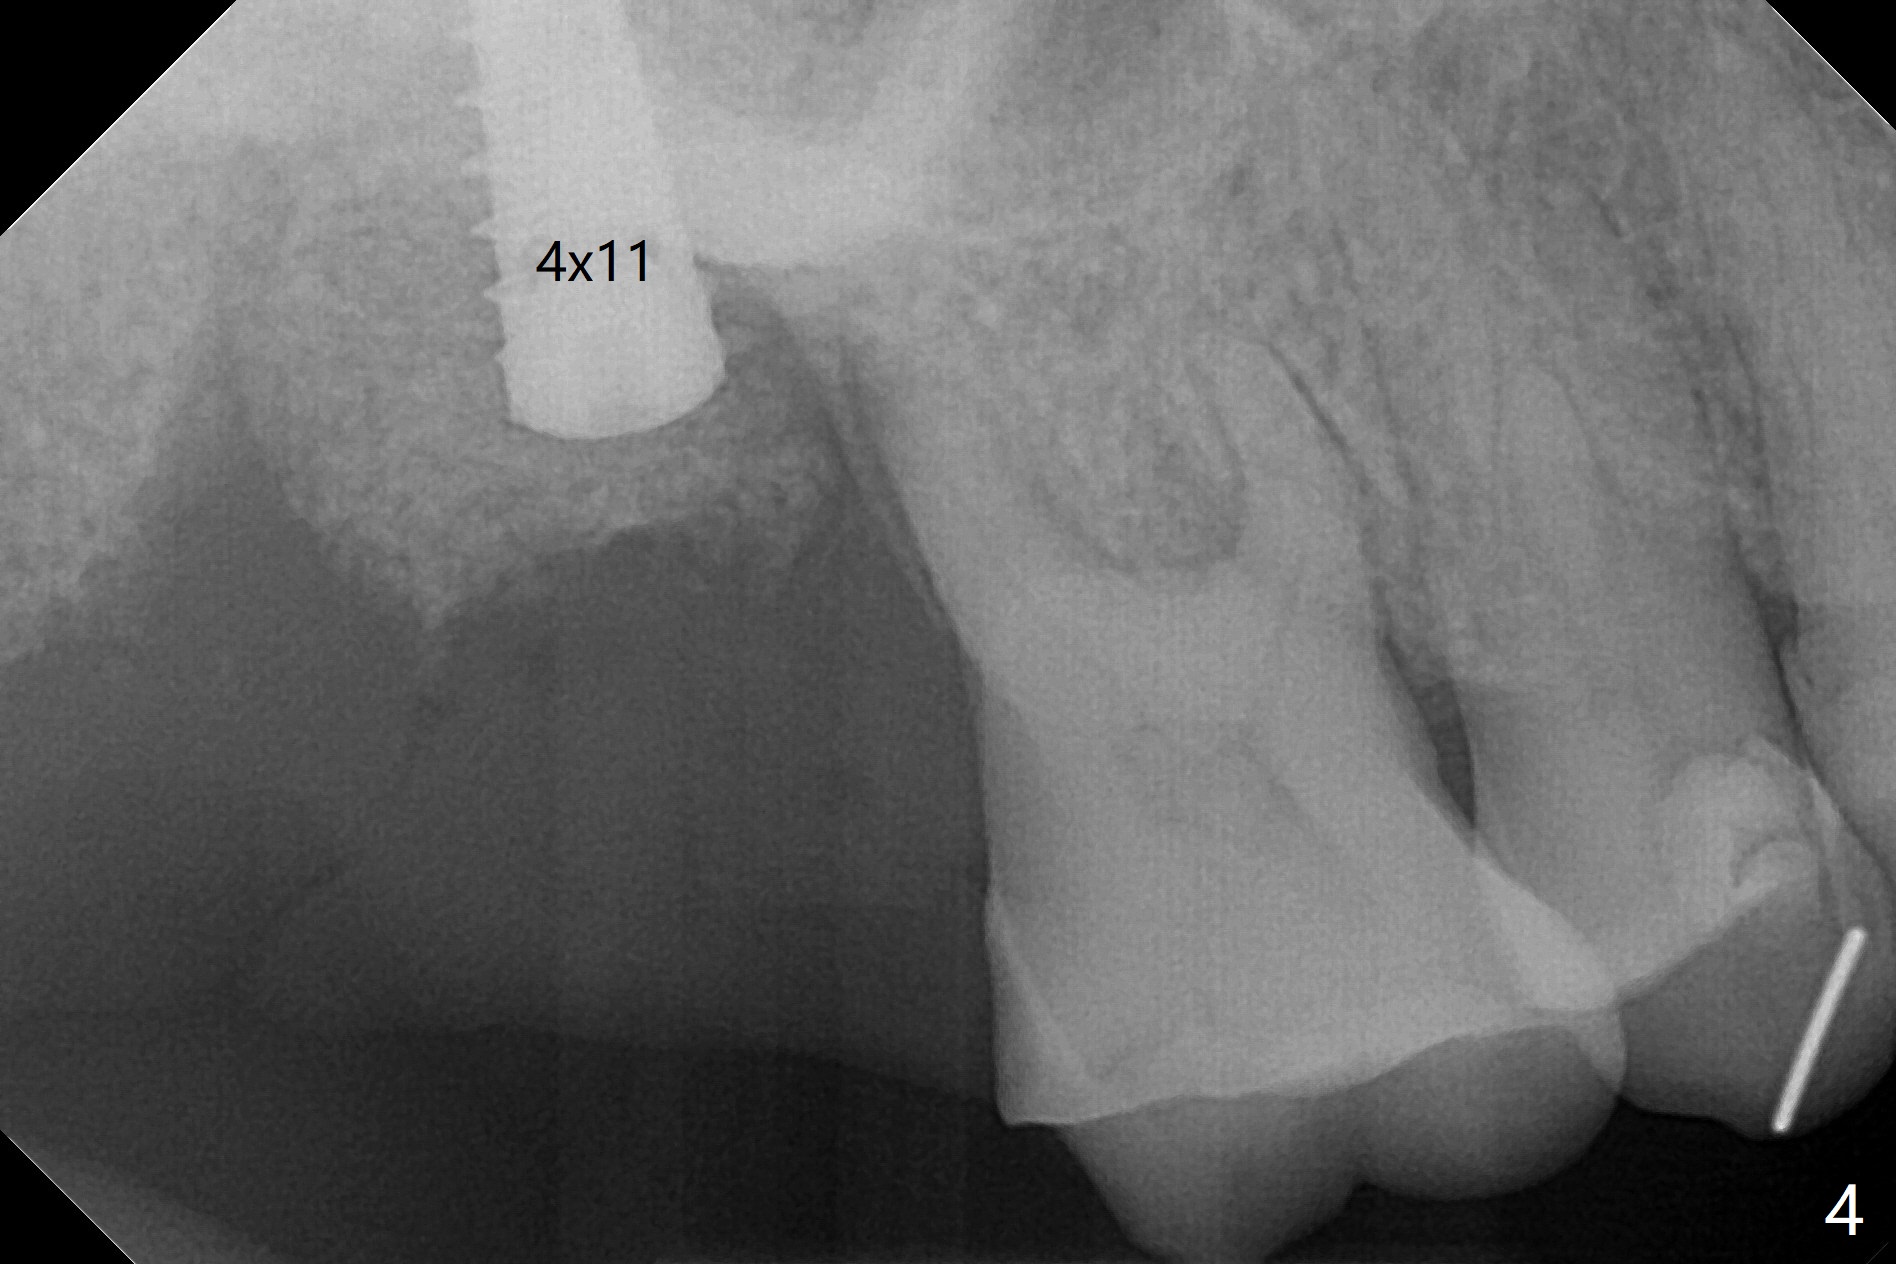

The offset is the distance from metal sleeve top to the fixture top (Fig.1). There are 3 kinds of offset options, 9 (standard), 10.5, and 12mm.When we raise the level of metal sleeve top from the soft tissue, then we’ll have more space between the metal sleeve top and the fixture top which means your bone trimmer & osteotomy drills need to be longer to compensate the vertical difference. 为了减轻张口度问题,预备两个导板,先用9毫米补偿导板(图二(理论上偏移会少些)):从2.2x7.3至3.0x10毫米钻头,但是插入3.0x11.5毫米钻头就有困难,所以接着使用6毫米补偿导板(图三)和3.0x8.5毫米钻头完成钻洞。不过又使用前个导板放置3.5x11.5毫米IS报废植体,扭力很低,用手指旋入,不假思索放置最终植体(4x11毫米),扭力仍低,增加植入深度接近3毫米,扭力没有明显提高,但是还稳定,不过放置修复基台,植体好像松动,只好取出,放置愈合帽。虽然植体植入太深些,但是有利于颊侧骨粉血供,因为颊侧牙龈明显退缩,植体稍微龈下,离颊侧牙龈大约3毫米。放置Vanilla粘性骨粉,两张PRF膜,以及树脂敷料。术后即刻根尖片显示植体似乎种得太深了(图四),不得不拍摄小范畴CT,原来植体往颊侧偏移,并且植入上颌窦(图五)。术后几小时没有鼻出血。术后一周复查正常。撤去树脂敷料后,重新插入导板,检查是否完全就位。一般树脂敷料撤除需要用手机切开,这次利用敷料薄,有一定弹性,一下子就把取出(图六)。敷料内侧是凹陷的(图七:*),说明手术时伤口放置过量PRF膜,但是术后一个月,伤口却是凹陷(图八(暴露愈合帽)),说明PRF溶解,骨粉遗失?少量骨粉附着于牙龈袖上。颊侧牙龈萎缩减轻了。